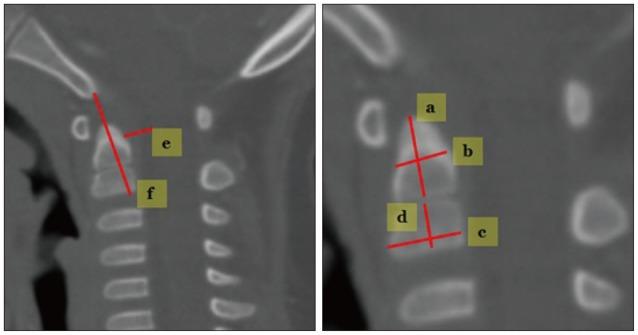

A total of 238 patients were included in this study, and mean age was 47.8±21.3 months. Spinal canal diameter, Power's ratio, McRae line, antero-posterior C1 ring height, atlantoaxial joint space, C2 growth, epidural space from the dens (M-PB-C2) and longitudinal distance (basion to C2 lower margin, B-C2) were measured. The mean value of each parameter was assessed for individual age groups. The cohorts were then divided into three larger age groups : infancy (I) (≤2 years), very early (VE) childhood (2-5 years) and early (E) childhood (5≥ years).

本研究共纳入238例患者,平均年龄为47.8±21.3个月。测量椎管直径、鲍尔氏比率、麦克雷线、C1环前后高度、寰枢关节间隙、C2生长情况、齿状突硬膜外间隙(M-PB-C2)和纵向距离(颅底至C2下缘,B-C2)。评估每个参数在各个年龄组的平均值。然后将队列分为三个更大的年龄组:婴儿期(I)(≤2岁)、极早期(VE)儿童期(2-5岁)和早期(E)儿童期(≥5岁)。